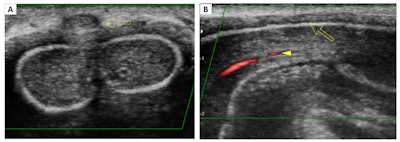

Superficial dorsal vein thrombosis. Color Doppler in transverse (A) and longitudinal (B) planes. The images show an absence of signal from the superficial dorsal vein of the penis and echogenic material related to thrombus (arrow). Presence of flow in the cavernous artery (arrowhead). All figures courtesy of Dr. Iñigo Zubiaguirre Telleria et al and European Society of Radiology (ESR) EPOS database.

Superficial dorsal vein thrombosis, or penile Mondor disease, is a benign and self-limiting process that affects sexually active men, especially during penile erection. It requires a clinical diagnosis (indurated cord on the dorsal aspect of the penis), but ultrasound helps to confirm the diagnosis and enables a follow-up to exclude a possible underlying tumor.

Ultrasound findings include absence of flow and compressibility of the superficial dorsal vein of the penis. "It is possible to identify echogenic material within the vein that confirms the thrombus. In some cases, an increase in the caliber of the vein and inflammation of the adjacent soft tissues are observed," Telleria and colleagues stated.